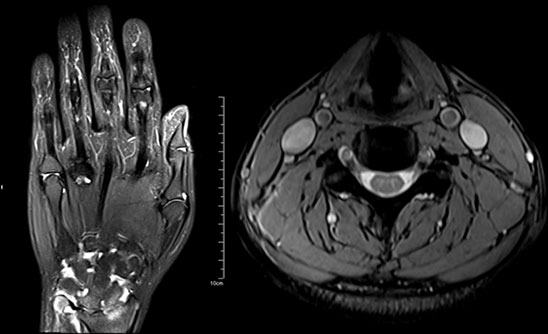

MAGNETOM Spectra 3.0T新一代聚能光谱磁共振

MAGNETOM Spectra 3.0T聚能光谱磁共振